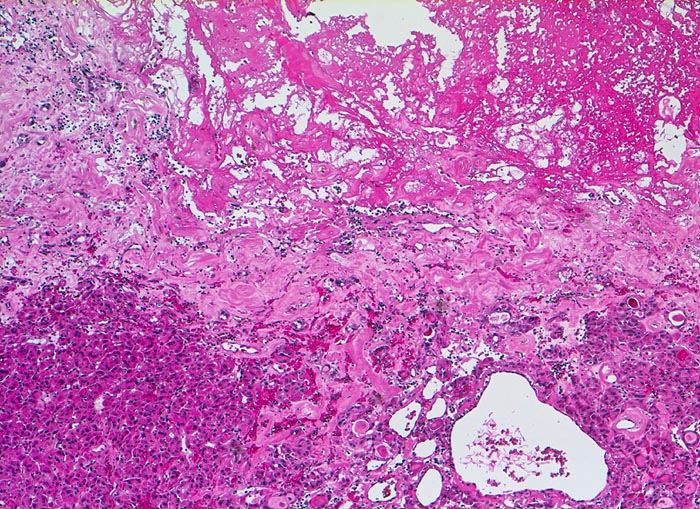

• Teils mikro- teils makrofollikuläre bekapselte Knoten.

• Tumorzellen ohne Kernatypien.

• Wenig Kolloid.

• Kapseldurchbrüche: Die breite bindegewebige Kapsel wird an mehreren Stellen pilzförmig vorgewölbt und an einigen Orten vollständig durchbrochen.

• Keine eindeutigen Gefässeinbrüche (keine Tumorthromben oder endothelialisierte Tumorzapfen in Venen der Kapsel oder jenseits der Kapsel). Das sollte der Kliniker dem Pathologen mitteilen: